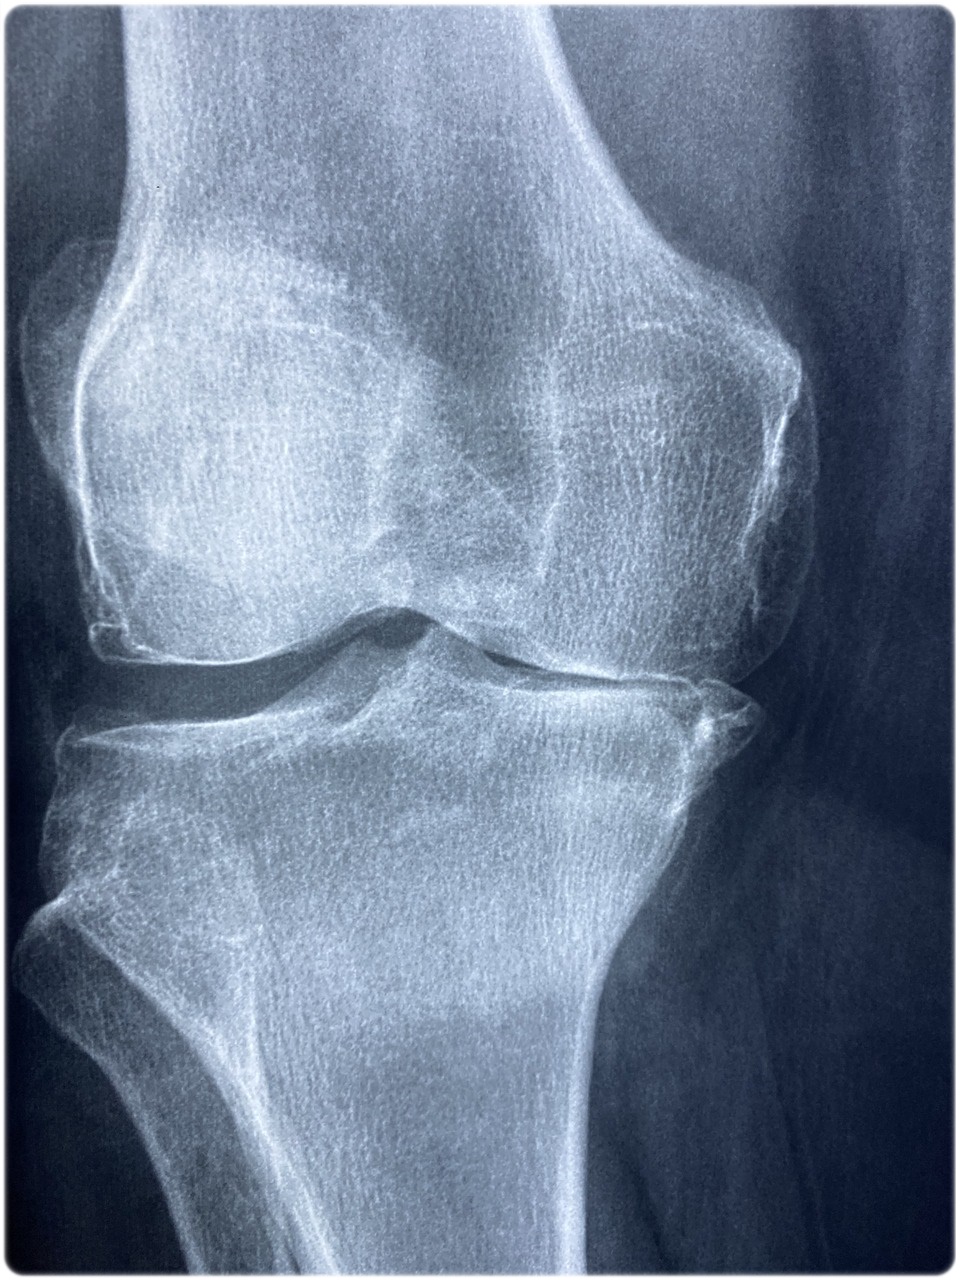

- 관절 통증과 붓기 : 관절이 붓고 통증이 발생합니다. 이때 류마티스 관절염의 특징은 '대칭적인 통증'이 자주 나타납니다. 보통 관절이 아플 때는 한쪽이 아픈 경우도 많은데, 양쪽이 모두 아픈 경우는 의심을 해볼 수 있습니다. 그리고 주로 손목, 손가락, 무릎등 관절에 영향을 많이 줍니다.

- 관절 변형 : 류마티스의 무서운 점은 관절을 변형시킬 수 있는데요. 무릎, 손가락등이 평소 가동범위만큼 나오지 않는다면, 크게 의심해보셔야 합니다.

- 관절 손상 및 변형 : 지속적인 염증으로 관절의 연골과 뼈가 손상이 됩니다. 시간이 지나면 관절의 모습까지 변형되어 영구적인 기능 상실이 됩니다.

- 관절 증상 평가 : 염증과 붓기가 심한지 판단하시고, 양쪽으로 무릎이 아픈지 확인해보셔야 합니다. 그리고 활동 중이 아닌, 아침에 뻣뻣함이 지속되는지 체크해 주세요.